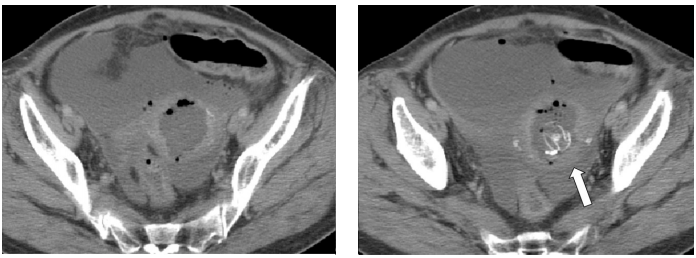

39 一位 46 歲女性因陰道出血及解尿困難、尿液滯留而到院就診,經陰道內診發現子宮頸有巨大腫塊, 其直徑超過 6 公分,表面呈潰爛之情形,且潰爛物侵犯前陰道壁。潰爛物經切片檢查病理報告為鱗 狀上皮癌,患者進一步接受電腦斷層掃描以診視局部侵襲狀況及淋巴結腫大情形,下圖為其電腦斷 層影像掃描之一,此電腦斷層影像中箭頭所指為何物?

(A)淋巴結 (B)子宮頸腫塊 (C)子宮肌瘤 (D)尿管及尿管球